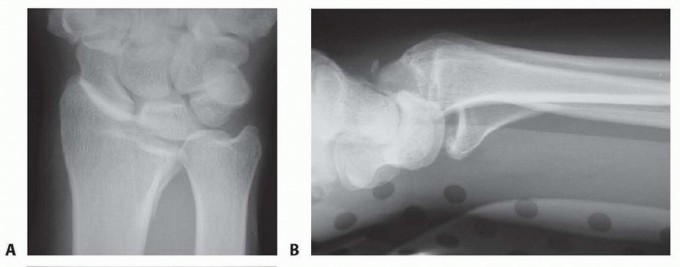

### FIG 5 • A. Carpal facet horizon (arrows). Used to differentiate between the volar and dorsal rim on the PA projection. B. Origin of carpal facet horizon. The carpal facet horizon is formed by that part of the articular surface that is parallel to the x-ray beam and depends on whether the articular surface is in volar or dorsal tilt. C. Normal teardrop angle. D. Depressed teardrop angle in this case is caused by axial instability of the volar rim. E. Normal articular congruency. F. Abnormal articular congruency, indicating disruption across the volar and dorsal surfaces of the lunate facet. G. AP interval is the point-to-point distance between the corners of the dorsal and volar rim. H. DRUJ interval. I. Normal lateral carpal alignment. J. Dorsal subluxation of the carpus. Congruency of the articular surface ( FIG 5E,F). The subchondral outline of the articular surface of the distal radius is normally both congruent and concentric with the subchondral outline of the base of the lunate; a uniform joint interval should be present between the radius and lunate along the entire articular surface. When the joint interval between these articular surfaces is not uniform, discontinuity and disruption of the lunate facet has occurred. Anteroposterior (AP) distance (normal: females 18 ± 1 mm, males 20 ± 1 mm; FIG 5G). The AP distance is the point-to-point distance from the dorsal to palmar rim of the lunate facet. It is best evaluated on the 10- degree lateral view. Widening of the AP distance implies discontinuity of the volar and dorsal portion of the lunate facet. 80 DRUJ interval ( FIG 5H). The DRUJ interval measures the degree of apposition between the head of the ulna and the sigmoid notch (normal: 2 mm or less). This parameter is best measured with the forearm in neutral rotation. Significant widening of the DRUJ interval implies disruption of the DRUJ capsule and TFCC. Coronal malalignment of the distal radial fragment is often suggested by widening of the DRUJ interval. Lateral carpal alignment ( FIG 5I,J). On the 10-degree lateral view and with the wrist in neutral position, the rotational center of the capitate normally aligns with a line extended from the volar surface of the radial shaft. Dorsal rotation of the volar rim results in a dorsal shift of lateral carpal alignment as the carpus subluxes dorsally. This may place the flexor tendons at a mechanical disadvantage, affecting grip strength. In addition to injury films, reassessing radiographs after reduction can be very helpful in determining the personality and specific components of a particular fracture. Computed tomography (CT) scans allow higher resolution and definition of fracture characteristics, particularly for highly comminuted fractures. Preferably, an attempt at closed reduction before obtaining a CT scan will help limit distortion of the image. CT scans are particularly helpful for visualizing intra-articular fragments as well as DRUJ disruption and incongruity of the sigmoid notch. Clinical evaluation of the carpus, interosseous membrane, and elbow, combined with radiographic studies when needed, should be included to identify the presence of other injuries that may affect the decision for a particular treatment. ## SURGICAL MANAGEMENT